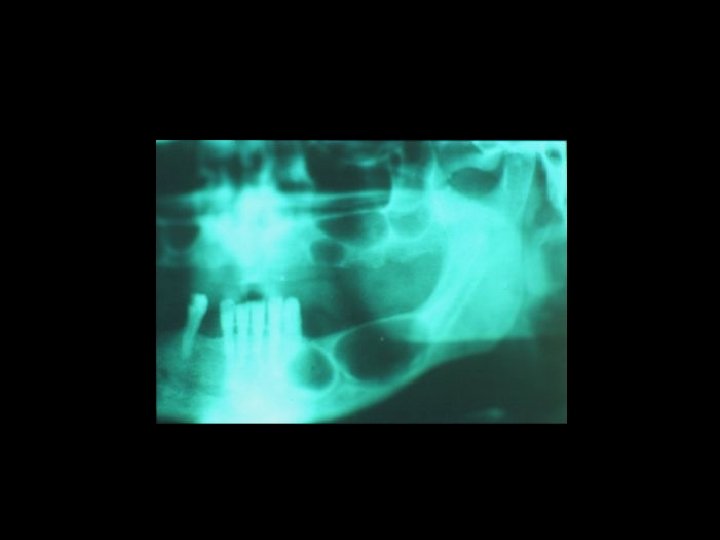

Il contenzioso PRINCIPALI AMBITI Ø Ø Ø La diagnosi La chirurgia orale La terapia conservativa Il trattamento delle anomalie dento-scheletriche La riabilitazione protesica

Responsabilità Ø Nel periodo pre-operatorio Ø Relativamente all’intervento Ø Nel periodo post-operatorio